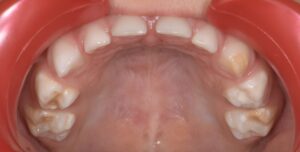

Le congrès de l’EAPD (Académie Européenne d’Odontologie Pédiatrique) a défini des critères de diagnostic en 2003. A savoir des opacités délimités, des fractures post-éruptives, des restaurations atypiques ainsi que que des extractions des molaires. (3) Le diagnostic différentiel doit surtout s’établir entre des amélogénèses imparfaites et des hypominéralisations d’origine traumatique pour les dents antérieures. Cliniquement, les dents vont présenter des colorations blanches ou brunes opaques sur une partie ou sur toute la surface de la dent (Figures 1-2-3-4).

formation dentaire pédodontie Figure 1.

MIH, état des lieux et thérapeutiques Figure 2.

Figures 1-2 : Incisives centrales atteintes de MIH